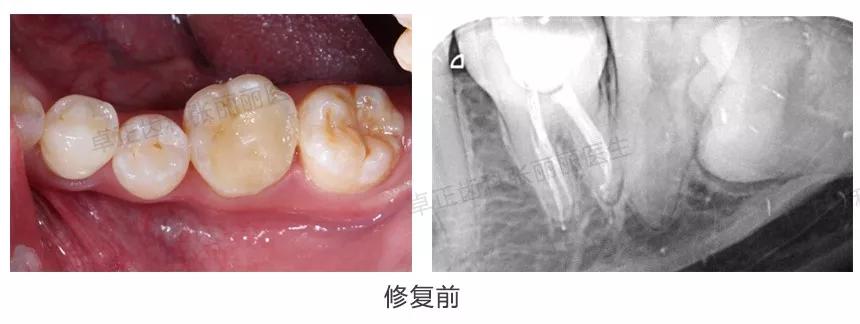

▍ 高嵌体(部分冠)

由于全冠修复需要磨除较多牙体组织,对于一些根管治疗后缺损范围不太大的后牙,为了尽量保存牙体组织,也可以采用覆盖全部面的高嵌体(部分冠)修复。

临床案例:左下6根管治疗后,采用覆盖全部面的高嵌体修复,相比全冠修复,牙体预备量减少。